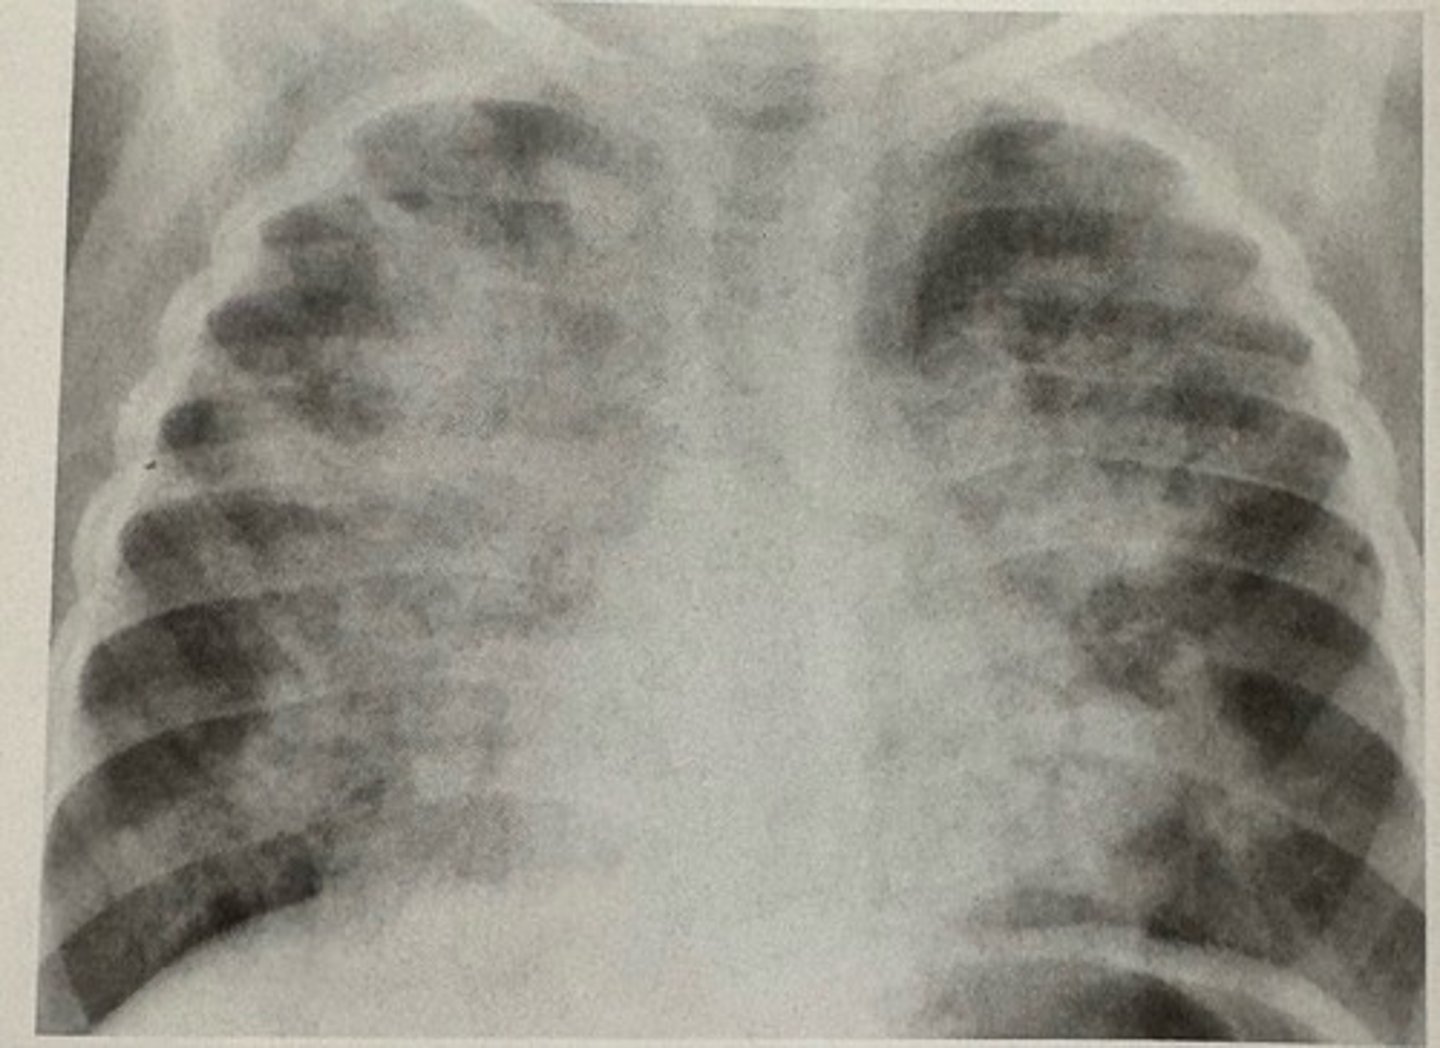

patent ductus arteriosus

what pathology is present?